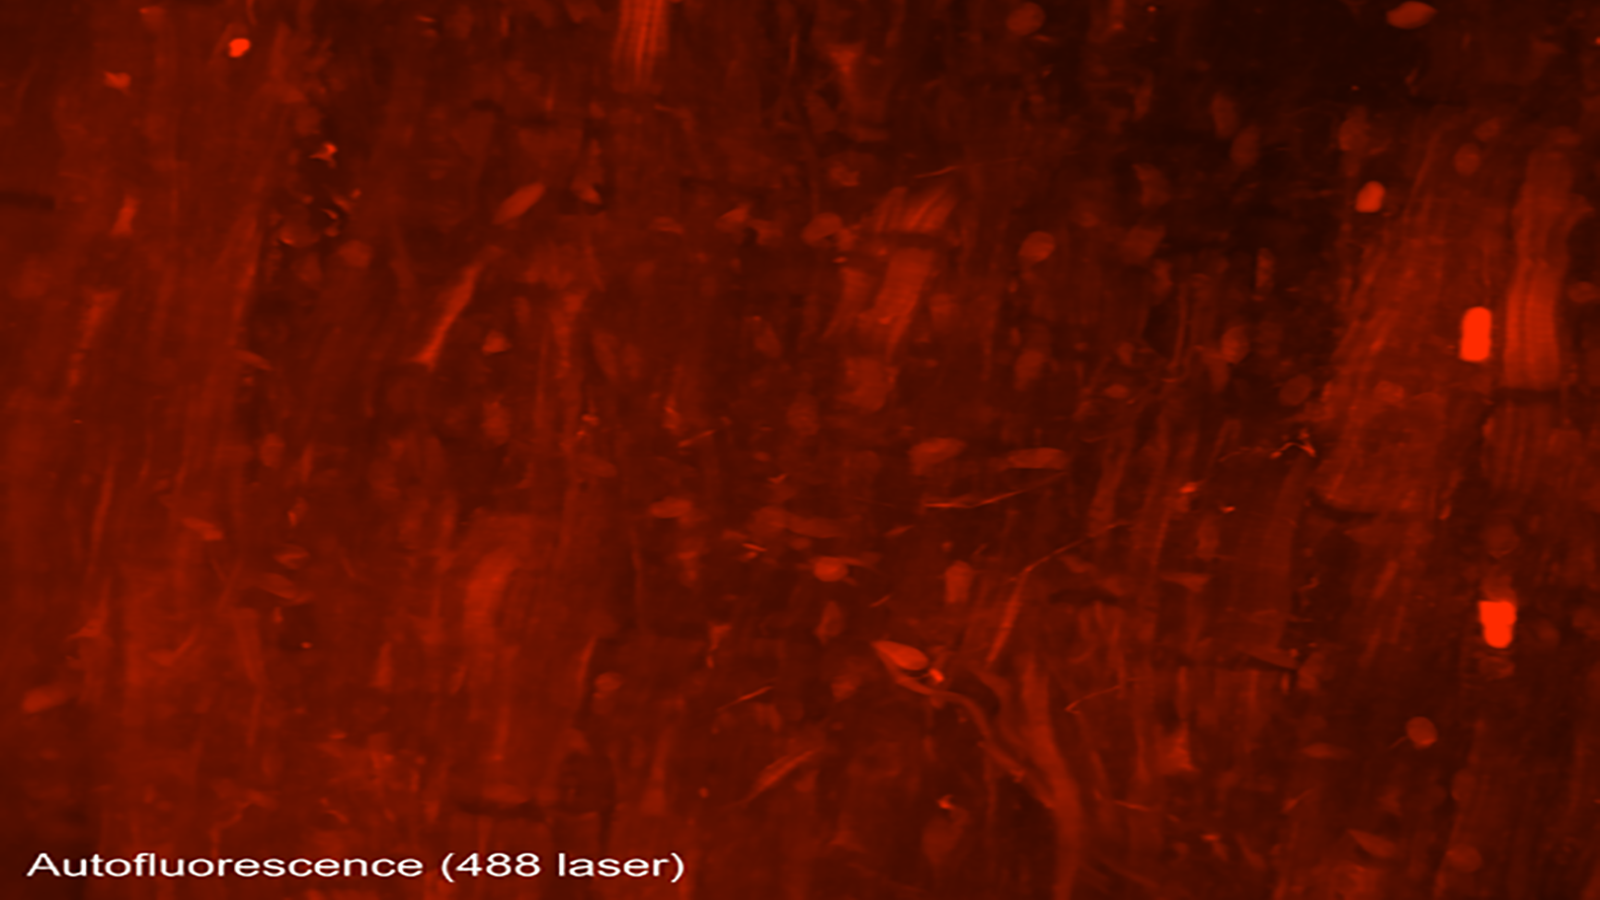

Autofluorescence image capturing heart cells (red), nuclei (blue), and dense fibers of the heart (green), courtesy of Dr. Seth Currlin at University of Florida

An autofluorescence image of cells that make up the heart/cardiac muscle, from Dr. Seth Currlin of University of Florida